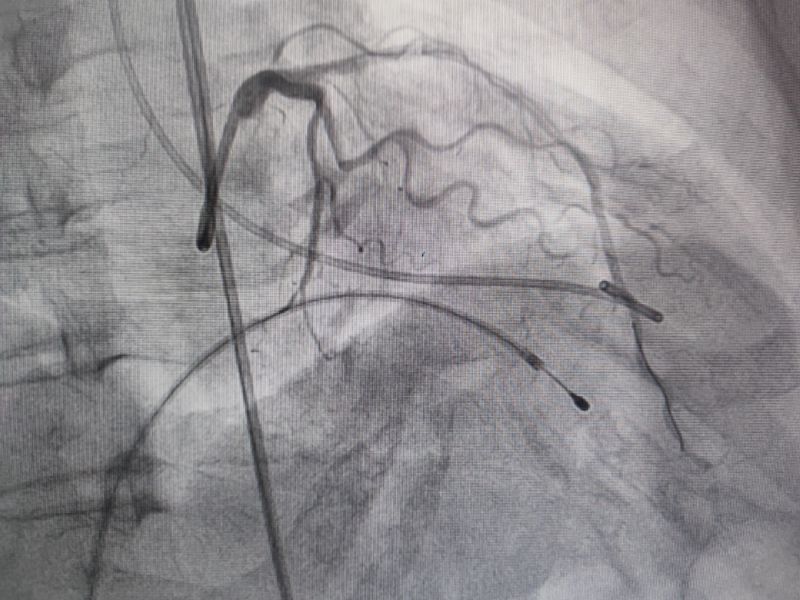

冠脈造影

經過多輪嚴謹的術前討論,在吳棟梁院長的專業指導下,崔旭輝主任醫師團隊決定在臨時起搏器的安全保護下,為患者實施冠狀動脈造影術及室間隔化學消融術。術中,團隊通過造影精準鎖定第一穿隔支為消融靶血管。測壓數據顯示:左室壓260/15mmHg,流出道173/6mmHg,主動脈壓106/70 mmHg,壓力階差達87mmHg。隨后,團隊使用2.0X15mm預擴球囊以8atm壓力阻斷第一穿隔支遠端血流1分鐘,再次測壓時,壓力從269/7mmHg驟降至174/4mmHg,這一結果充分證實該血管正是室間隔的有效供血血管。緊接著,團隊通過SPRINTER OTW2.0×8mm球囊緩慢注入1.4ml無水酒精。10分鐘后復測,左心室壓降至136/5 mmHg,主動脈壓為112/93 mmHg。術后第2天,王女士胸悶、氣短、心悸等不適癥狀完全消失。復查心臟彩超顯示:EF值與FS值保持穩定,收縮期左室流出道血流速度降至252cm/s,PG值為25mmHg。